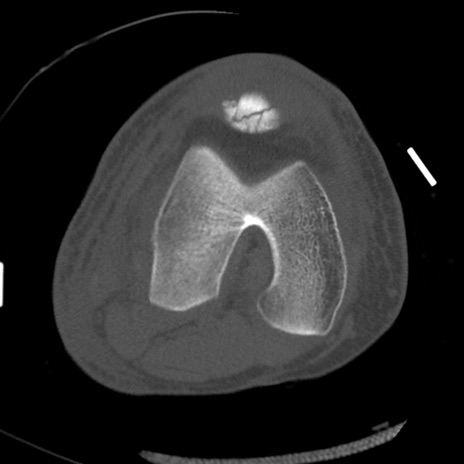

症例28 右膝関節CT(横断像)

右膝関節CT